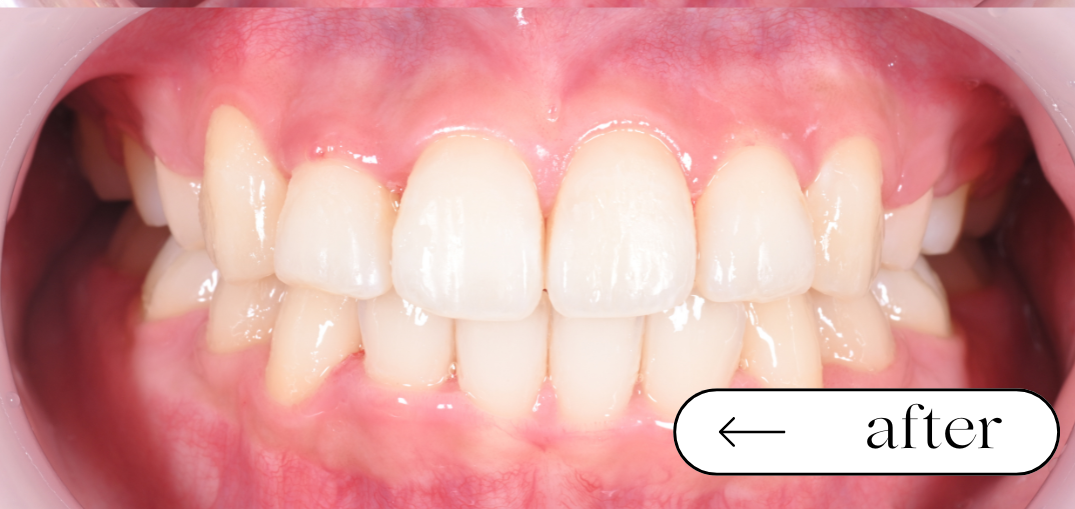

八重歯や前歯のガタガタが気になる、横顔をすっきり見せたいとのことで来院されました。便宜抜歯(4本)と全顎矯正を行い、歯並びとかみ合わせ、口元のバランスの改善を目指しました。

治療期間・回数

期間:2年2ヶ月 回数:月1回受診

- 全顎矯正治療(Ⅱ期治療) 700,000(税込 770,000)

- 便宜抜歯 1歯あたり 11,000 (計)4本 44,000

便宜抜歯を伴う全顎矯正では、痛み・腫れ・出血・感染などが生じる可能性があります。また歯の移動に伴い、歯根吸収や歯ぐきの変化、後戻り、治療期間の延長などが起こる場合があります。